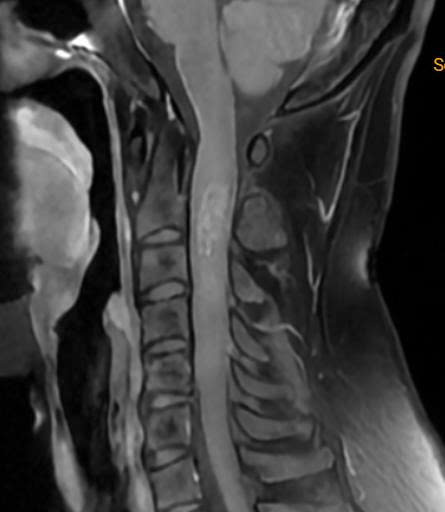

Khối u tủy hiếm khi gây liệt tứ chi một cách đột ngột. Sự tiến triển thường diễn ra âm thầm cho đến khi nó chèn ép đủ lớn để đánh sập toàn bộ hệ thống vận động. Thế nhưng, đó lại chính xác là những gì đã xảy ra với người phụ nữ 39 tuổi (quê Nghệ An).

Nhận định đây có thể là tình trạng u chảy máu, tạo áp lực cấp tính lên tủy sống, bác sĩ Hùng lập tức yêu cầu đưa người bệnh ra Hà Nội ngay trong đêm. Thời điểm bệnh nhân có mặt tại viện, ê-kíp cũng đã sẵn sàng đón lõng để tiến hành chụp chiếu kiểm tra tức thì.

U tủy cổ là một bệnh lý tương đối hiếm gặp trong thực hành lâm sàng, nhưng lại mang đến thách thức cực đại cho các phẫu thuật viên. Tủy sống đoạn cổ không chỉ là con đường độc đạo truyền tín hiệu vận động cho toàn bộ cơ thể từ cổ trở xuống, mà còn là nơi chứa các trung tâm sinh tồn cốt lõi điều khiển nhịp tim và nhịp thở.

Chỉ một sai sót nhỏ bằng milimet trong quá trình bóc tách, hoặc sự chèn ép vô tình do dụng cụ phẫu thuật, bệnh nhân có thể vĩnh viễn không thể tự thở, đối mặt với nguy cơ thở máy suốt đời hoặc ngừng tim ngay trên bàn mổ. Chính vì ranh giới quá đỗi mong manh này, can thiệp vào tủy cổ vẫn luôn được xem là vùng "tử địa" mà nhiều bác sĩ Ngoại Thần kinh ái ngại.